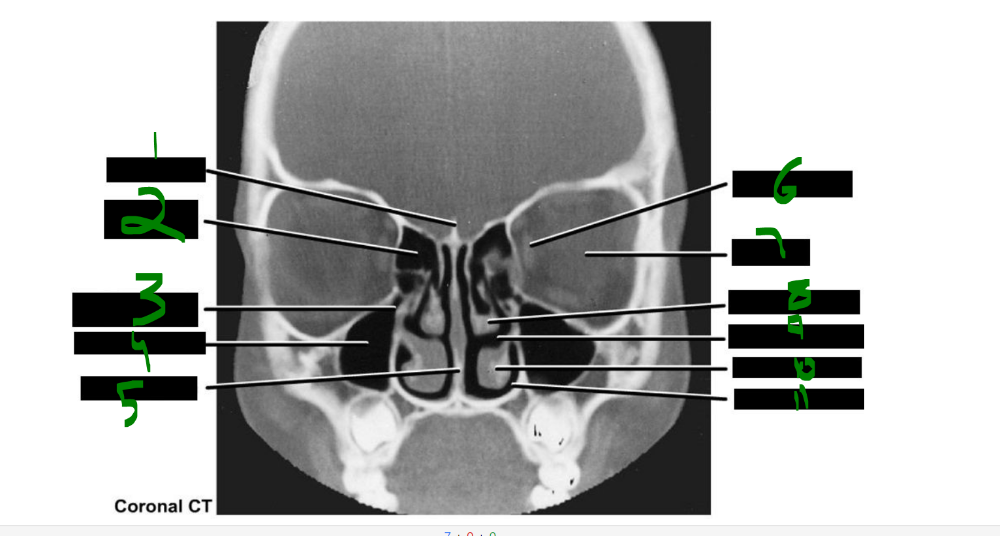

orbit

What is 1?

crista galli

37

What is 2?

ethmoidal cells

card image

What is 3?

opening of maxillary sinus

What is 4?

maxillary sinus

infraorbital

What is 5?

nasal septum

38

What is 6?

medial rectus

What is 7?

eyeball

What is 8?

middle concha

piriform aperture

What is 9?

middle meatus

39

What is 10?

inferior concha

What is 11?

inferior meatus